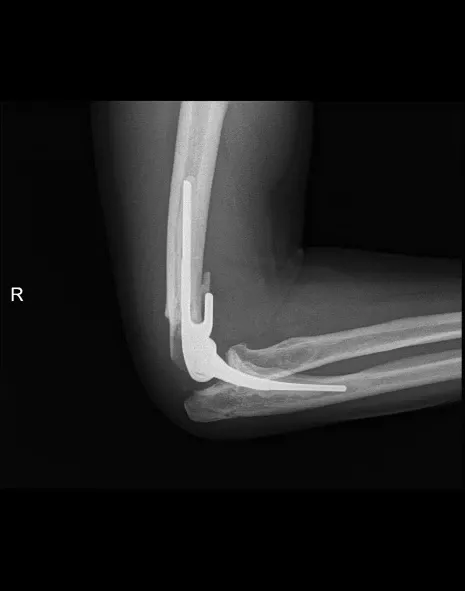

Elleboogartrose

Omschrijving

Elleboogartrose is slijtage van het kraakbeen, wat leidt tot ontsteking en pijn in de elleboog.

Klachten

- Pijn en zwelling

- Stijfheid en verminderde beweeglijkheid van de elleboog

- Soms nachtelijke pijn

Behandeling

- Pijnstillers, ontstekingsremmers, aanpassen activiteit/belasting van de elleboog

- Cortisone-inspuiting

Bij ernstige slijtage:

- Elleboogprothese

- Of radiuskopprothese wanneer slechts een deel van het gewricht is aangetast

Nabehandeling

Korte immobilisatie, daarna progressieve mobilisatie en vaak kinesitherapie. Revalidatie: 3 tot 6 maanden. Protheses geven meestal goede pijnverlichting; beweeglijkheid verbetert in mindere mate.